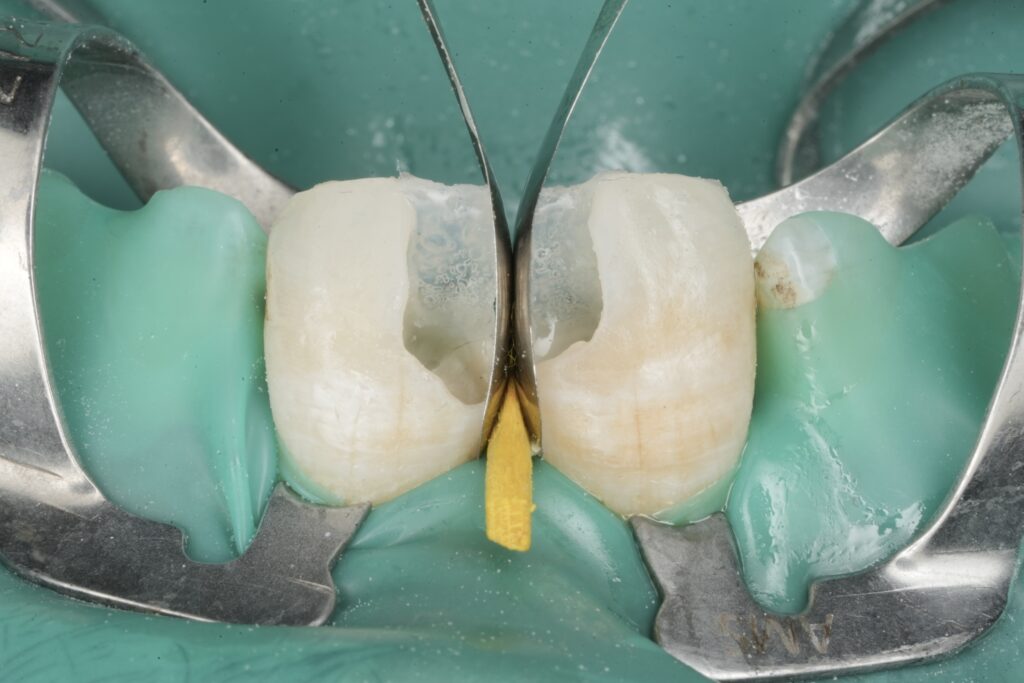

3) Pre-wedge and contact strategy (before cutting more)

Before aggressive refinement, pre-wedging helps:

- protects the papilla

- slightly separates teeth (improves final contact)

- creates a better cervical seal for the matrix

This is one of the simplest ways to avoid the classic Class II disaster: flat contour + weak contact.

References: (Sectional matrix/contact literature and clinical consensus) Loomans et al.; El-Mowafy et al.